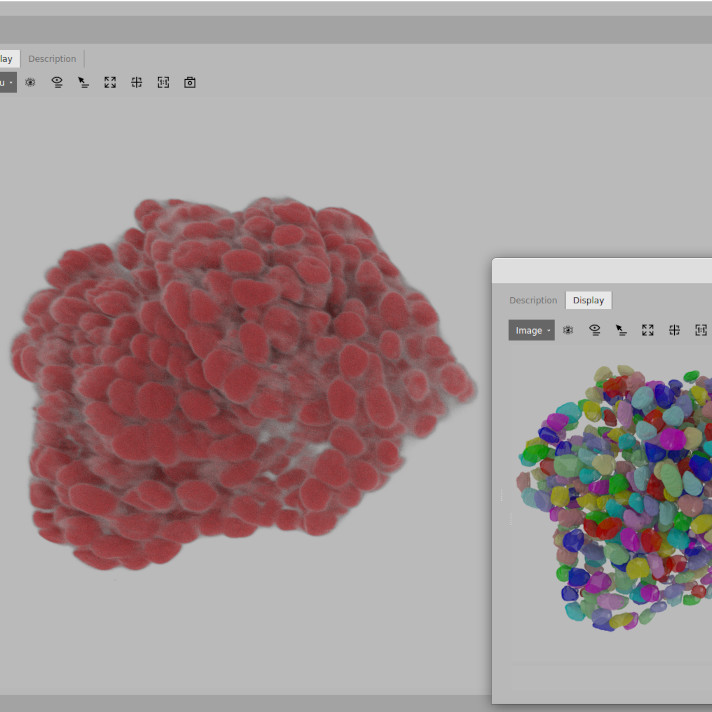

2 Detection and segmentation

- Cell and object detection/segmentation – Identifying and segmenting structures within images.

BIAS supports both classical segmentation methods (f.x. auto-thresholding) and modern deep-learning-based models based cellular or subcellular structure segmentation models.

- Our generic models can handle a wide range of imaging modalities.

- We also offer specialized models tailored for specific tasks.

For phenotype classification, BIAS provides an interactively trainable system that supports both feature-based and image-based algorithms. Users can customize classification models to fit the specific needs of their project.